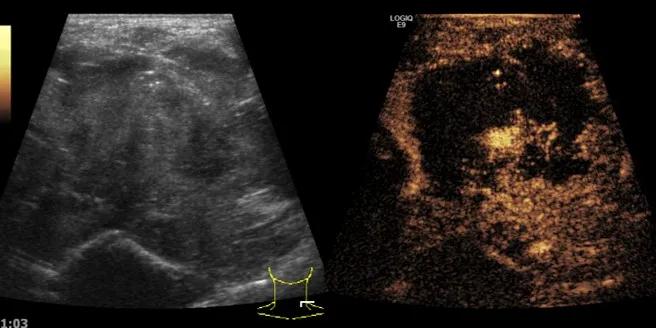

第三例是甲状腺癌患者,双侧甲状腺癌切除术后、碘治疗后一年余效果欠佳,超声显示左颈3区3枚低回声结节,穿刺示甲状腺乳头状癌转移。患者不愿意手术,希望采取局部治疗。对病灶进行液体隔离后采取热消融术,由于淋巴结较小,热消融一分钟左右完全灭活,术后增强影像显示没有脏器充填。

(病例3图例)